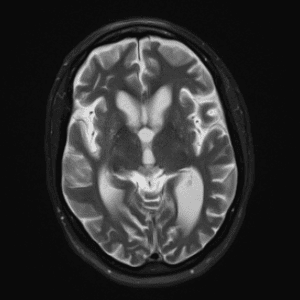

Neurodegenerative Diseases